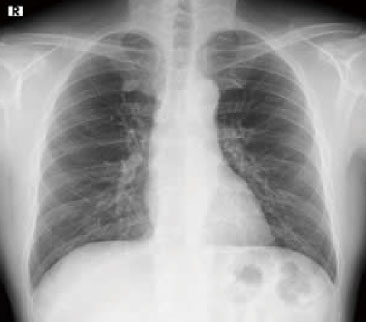

一般撮影

一般撮影とは

一般撮影は、レントゲン検査やⅩ線撮影と呼ばれることもあり、胸部、腹部、骨など全身各部位の撮影を行います。

Ⅹ線という放射線を人体に照射して透過したⅩ線を画像にします。

検査時間は、部位や撮影回数により異なりますが5~10分程度です。

胸部